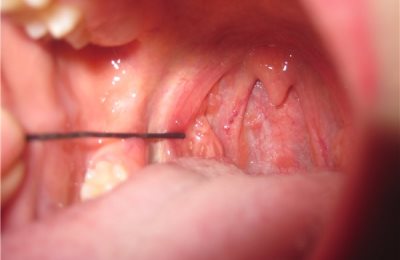

Ранки в полости рта

Ранения горла бывают наружные и внутренние, проникающие и непроникающие, изолированные и сочетанные, слепые и сквозные.

Симптомами чаще всего являются кровотечение, нарушения дыхания, речи, затруднение глотания из-за «кома», удушье, выраженный болевой синдром.